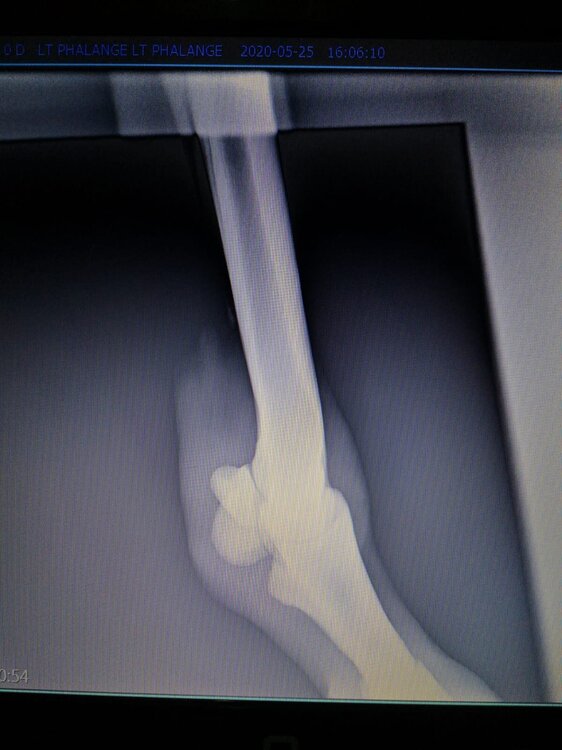

Salve volevo chiedervi qualche informazione in merce tò a un problema che ho avuto con la mia puledra. Qualche settimana fa mentre stavo lavorando alla corda è scivolata urtato l'arto posteriore sinistro. Arrivati in box ho messo dell'acqua a pressione perché si era gonfiato sia il nodello sia il pastorale. Già l'indomani l'arto era sgonfio ritornato normale, quindi ho continuato a lavorarla. Ma dopo qualche giorno di lavoro alla corda leggerissimo, al rientro in box ho notato che sia il nodello che il posturale gonfiavano nuovamente. Allora ho chiamato il veterinario che ha detto che la cavalla aveva una lussazione e mi ha insegnato come cura una fasciatura con della creta per 24h per cinque giorni e un antinfiammatorio. Dopo un paio di giorni la fasciatura ha fatto come delle vesciche e il gonfiore è aumentato dal pastorale alla garra. Abbiamo chiamato un altro veterinario abbiamo fatto vedere anche a lui la cavalla e diceva che poteva essere la frattura del ditino, ma si dovevano fare le lastre per essere sicuri. Ora abbiamo fatto le lastre e il radiologo dice che c'è dell'infiammazione ma non c'è niente di grave. Il veterinario,viste le lastre dice che deve essere operata. Allora abbiamo consultato un'altro veterinario che dice che la cavalla non ha assolutamente niente. Ora io vi allego le radiografie, datemi un vostro parere perché non só più cosa fare. Grazie